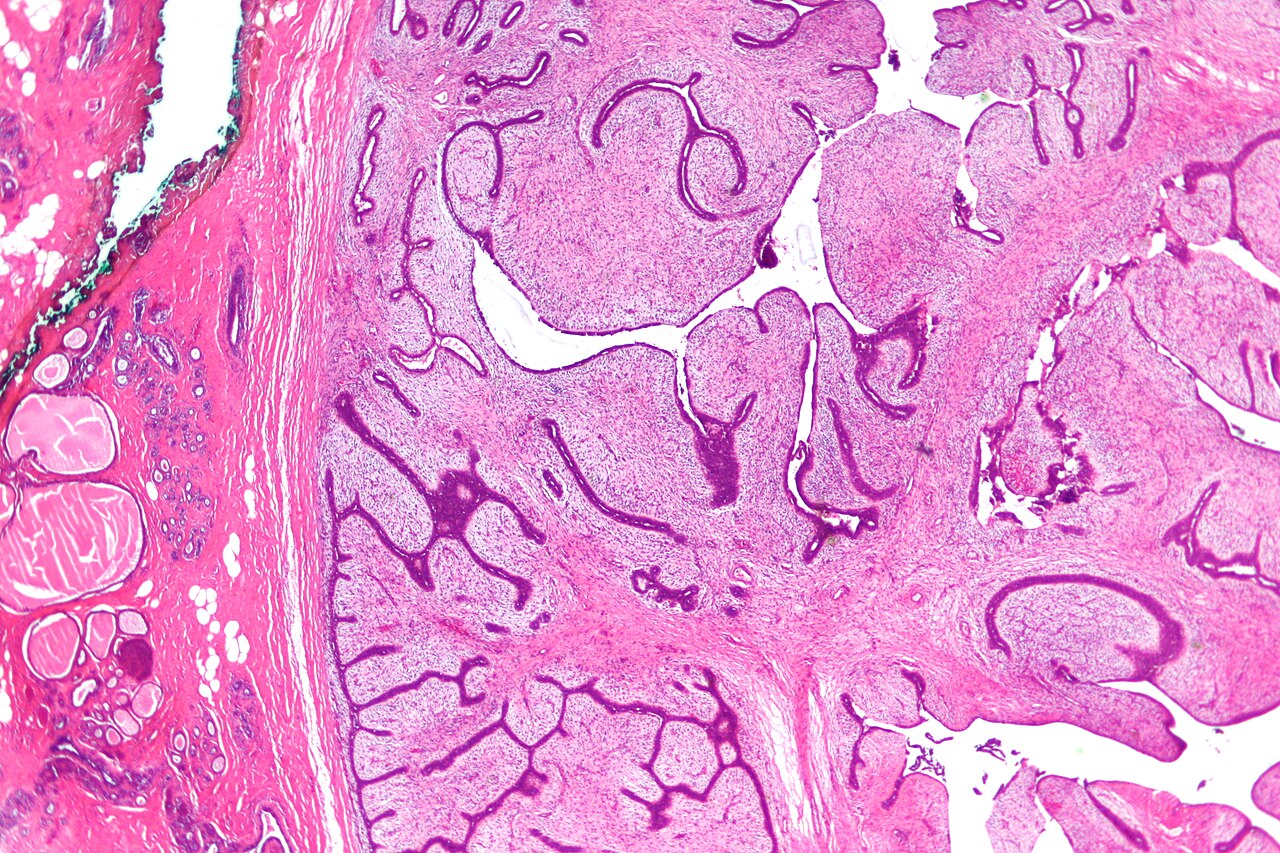

U nhú ở vú là một nhóm u không đồng nhất được đặc trưng bởi cốt lõi đư...

U phyllodes là một loại khối u xơ biểu mô hai pha hiếm gặp hình thành từ các t...